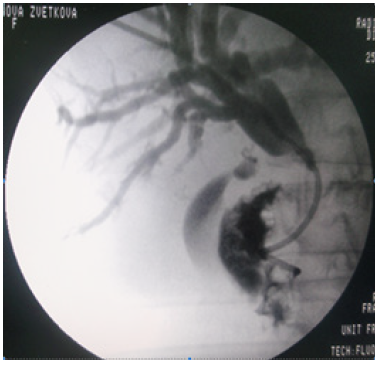

We completed that abdominal collection drainage with a percutaneous biliary drainage in the case of CBD stones and cholangitis associated with necrotic pancreatitis (Figure 9).

The indication for Percutaneous Biliary Drainage (PBD) is the same as an ERCP, which is the gold standard for the treatment of CBD stones. We apply the PBD in the setting of cholangitis, biliary obstruction and suspected choledocholithiasis [17].